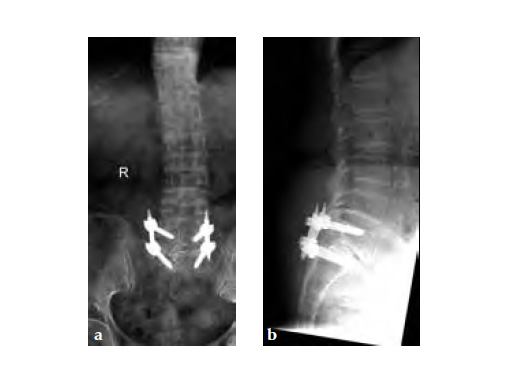

The patient underwent left L5S1 minimally invasive TLIF with pedicle screws 2 years ago for left lumbar 5th radiculopathy. At the same time she was put on fosamax for osteoporosis.

Case provided by Merng Koon Wong, Singapore, Singapore

Three weeks prior to her last admission, she complains of recurrent right thigh pain for which epidural analgesics were administered for presumed radiculopathy, however preliminary x-rays and even MRI of the thigh were also taken in view of her primary complaint regarding her right thigh. These investigations did not indicate the possibility of impending bisphosphonate related femur fracture. It is clear from the radiographs that she has an obvious anterolateral bow of her femur and a thickened lateral cortex in the lateral midshaft cortical bone, which may indicate a stress fracture (see Fig 3a-b).